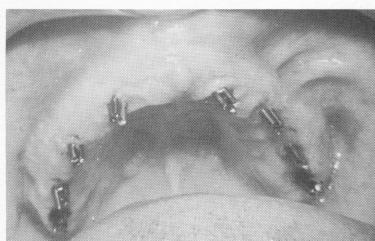

Fig. 10-216. The pins were affixed to one another by placing Teflon cylinders (exhibiting three parallel holes along their entire internal structures) over them with the aid of acrylic. (Courtesy I. Lew.)

5 Dental pins in upper jaw affixed to each other using Teflon cylinders